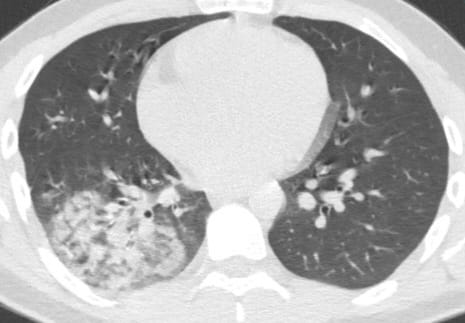

Prof. Dr. Özkaya, yaz aylarında klima kaynaklı zatürre vakalarının arttığını vurguladı. Ateş, uzamış öksürük, kas ve eklem ağrıları ve halsizlik şikayetleri olan hastaların büyük bir kısmında zatürre teşhisi konuluyor. Özellikle klima çarpması ve soğuk içeceklerin tüketimi, bu hastalığın yayılmasında önemli rol oynuyor.

Zatürre belirtileri arasında yüksek ateş, sürekli öksürük, kas ve eklem ağrıları ve halsizlik bulunur. Bu belirtiler görüldüğünde hemen bir sağlık kuruluşuna başvurulması ve gerekli tetkiklerin yapılması önemlidir.